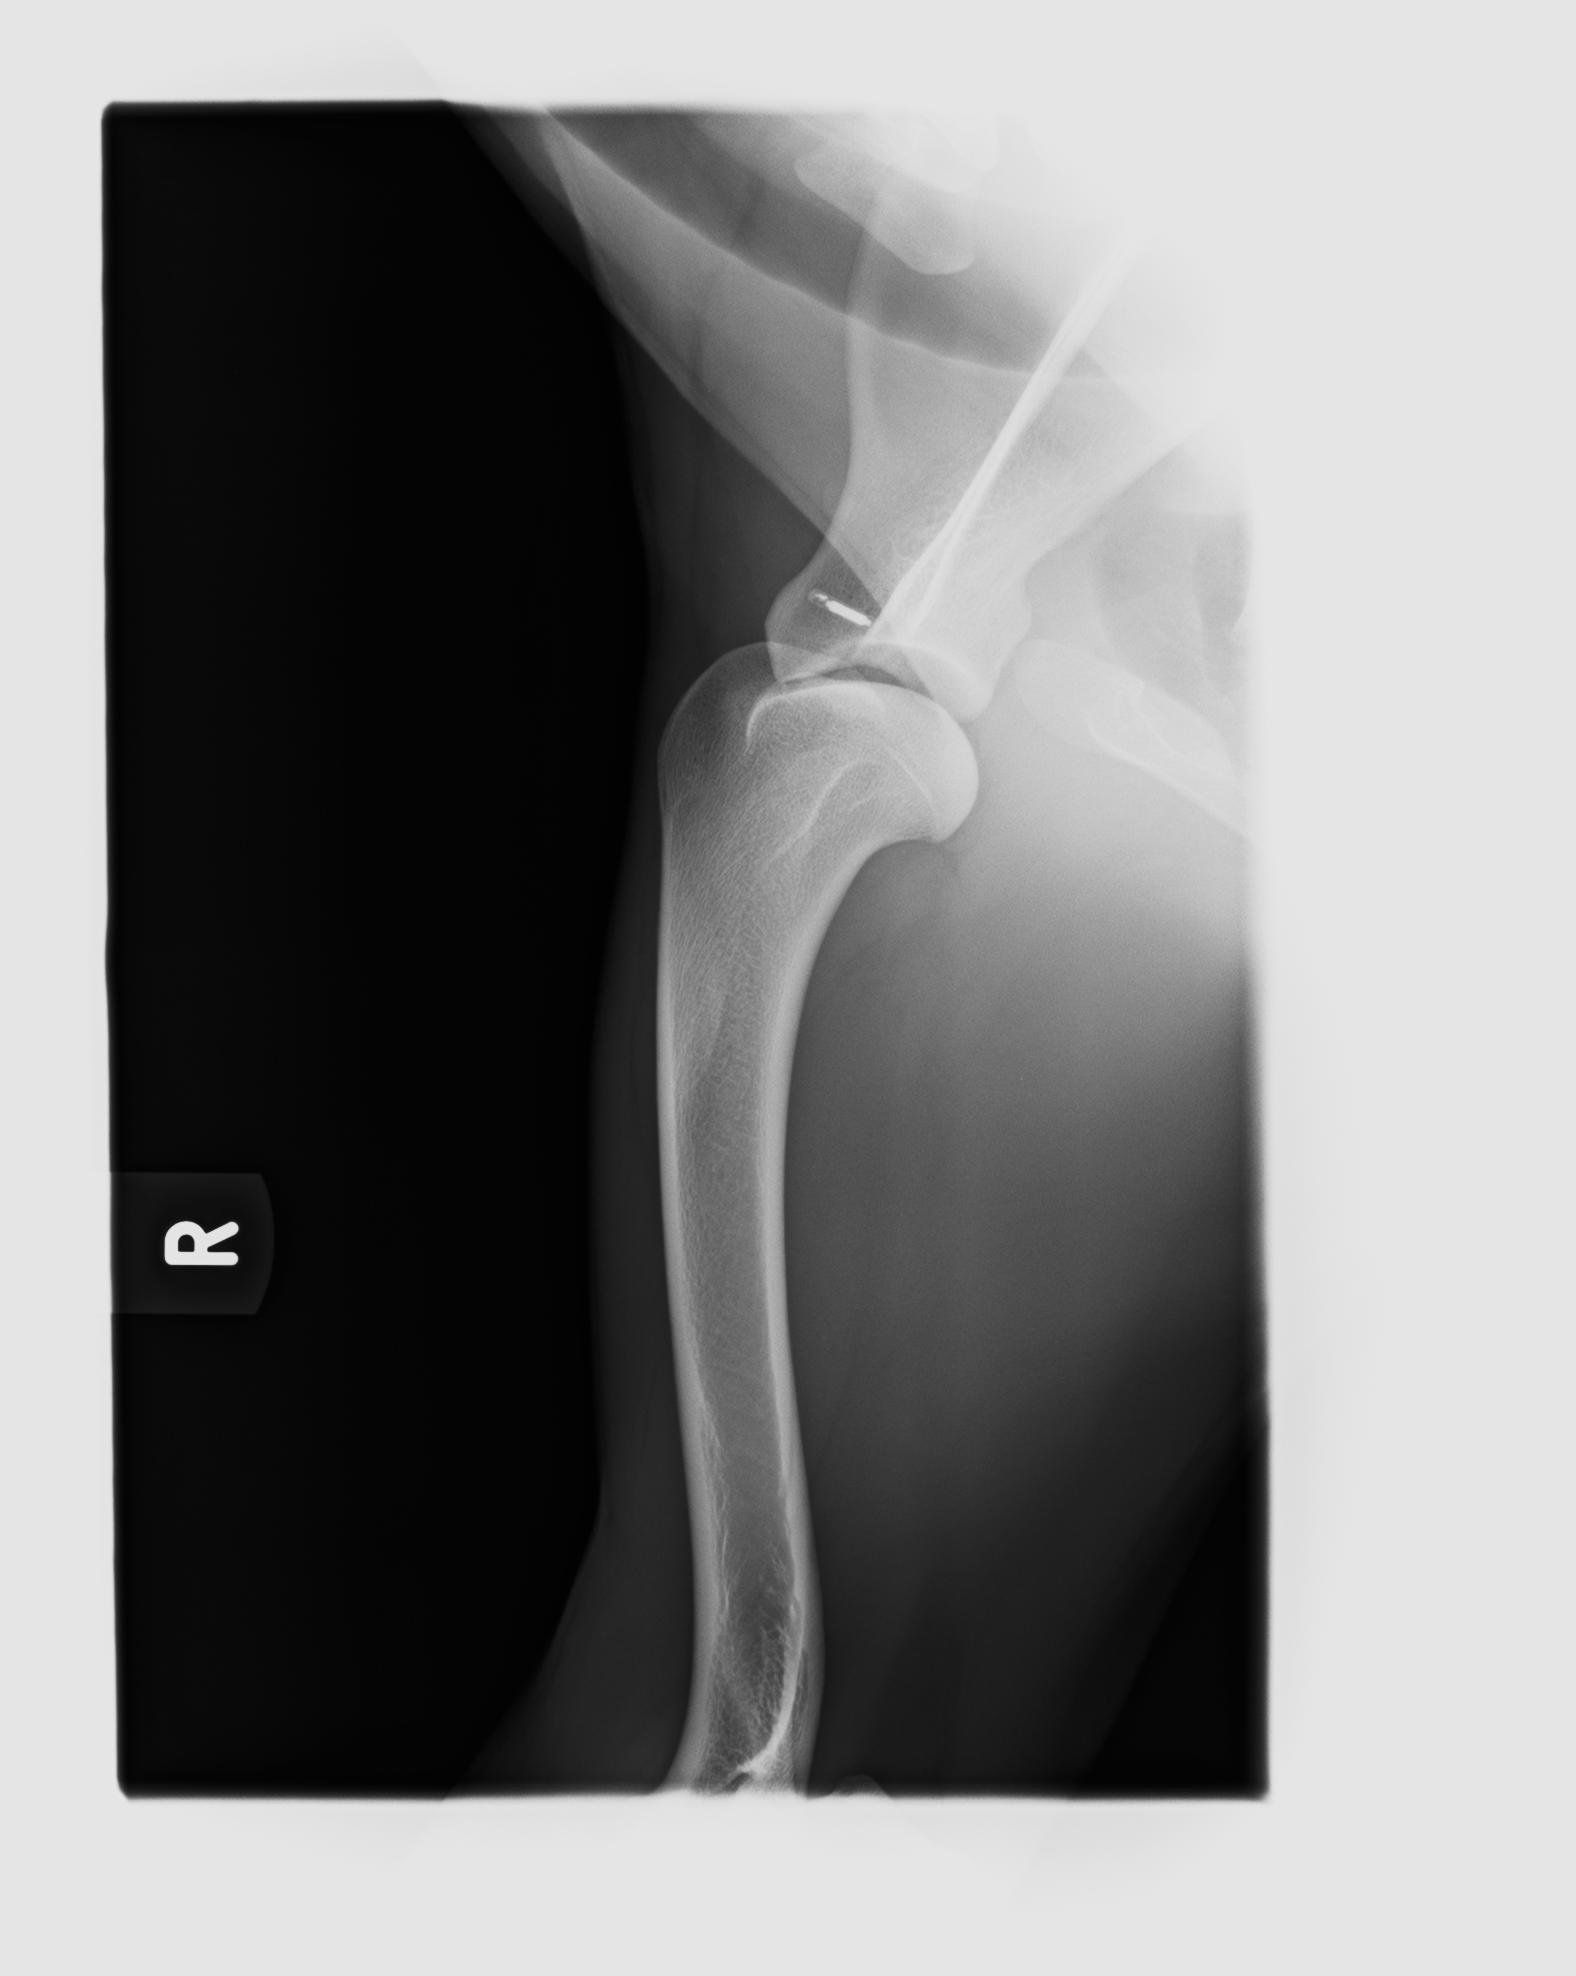

OCD der Schulter - Osteochondrosis dissecans

Bei einer OCD der Schulter kommt es zu einer Störung der Verknöcherung im Bereich des Oberarmkopfes, die in der Hälfte der Fälle an beiden Schultern auftritt. Betroffen von der OCD der Schulter sind vor allem Hunde großer Rassen, und hier mehr Rüden als Hündinnen.

Die ersten Lahmheiten treten meist schon mit vier bis acht Monaten auf, seltener erst mit zwei bis drei Jahren. Die Diagnose wird röntgenologisch gestellt. Ob chirurgisch oder konservativ therapiert werden sollte, wird heutzutage noch kontrovers diskutiert und ist nur individuell für den jeweiligen Patienten zu beantworten.

Eine Osteochondrose ist eine Störung der Umwandlung von Knorpel zu Knochen im Wachstum, „dissecans“ heißt „zerschneidend“. Bei der OCD führt dies zum Absterben von Knochengewebe direkt unterhalb des – gesunden - Gelenkknorpels. Erst als Folgeerscheinung der Knochen-zersetzung kommt es später auch zu Schädigungen des Gelenknorpels. Die OCD tritt bei Hunden v.a. in der Schulter auf, ist aber auch in anderen Gelenken – z.B. im Ellbogengelenk – möglich.

Das Bild zeigt eine OCD freie Schulter.